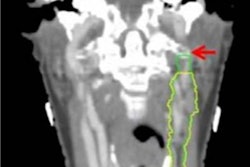

To help answer the question of which modality offers the best option, the researchers compared FDG-PET/CT with DWI-MRI among patients with suspected local recurrence of HNSCC after radiotherapy with or without chemoradiation.

MRI scans were performed on a 3-tesla system (Intera NT, Philips Healthcare) with a dedicated head and neck coil. The protocol included transverse T1-weighted turbo spin echo (TSE) before and after gadolinium and echo-planar DWI-MRI. FDG-PET/CT imaging was performed on a whole-body scanner (Biograph mCT, Siemens Healthineers) approximately one hour after injection of 2.0 MBq/kg of FDG and after a six-hour fasting period. Median time between the MRI and FDG-PET/CT exams was one day (range, 0-31 days).